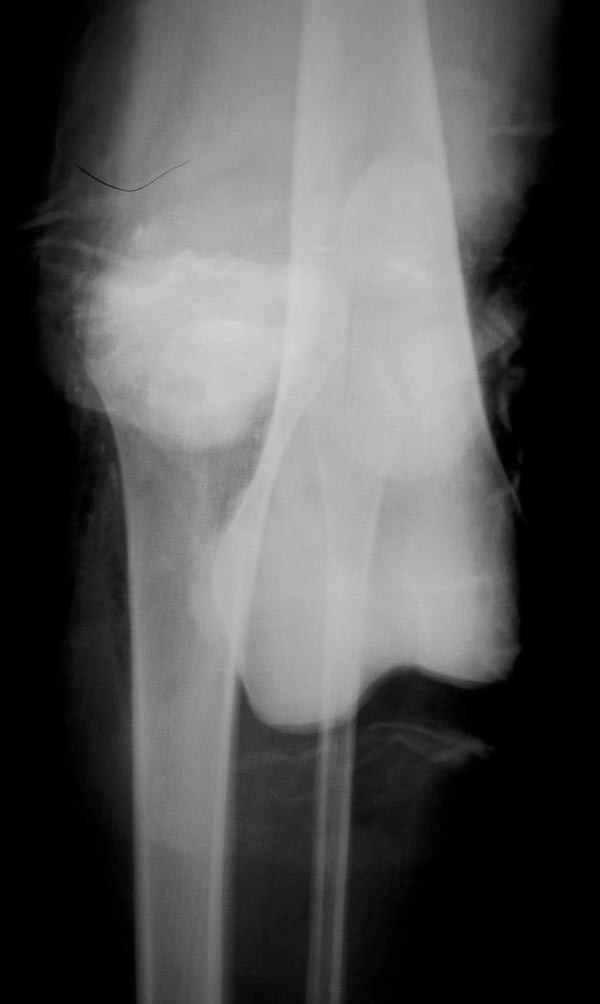

В приемное отделение поступает больная 22 лет, во время аварии ремень безопасности не был пристегнут, в крови большое количество кокаина.В приемном срочная интубация и седация, сделаны снимки.Диагностирован: открытый вывих левого коленного сустава.

Заключительный диагноз: Открытый вывих коленного сустава, перелом надколенника, разрыв собственной связки надколенника

На операции: Irrigation&Debridment около 10 литров раствора, по два стержня в сегменте, фиксация диагонального, с дефектом, перелома надколенника тремя cannulated 4мм шурупами, ушивание поперечного разрыва связки 5.0 Ethibon sutures, разрыв находился на 2 см ниже надколенника (срез чем-то острым), повторная ирригация раны, взятие посева на аэробическую и анэробическую культуру, окончательная фиксация стержней наружного фиксатора 50см Carbon Fiber Bars, вакуумное закрытие. Мониторинг показал, что компартмент синдрома нет.

Сегодня досылаю остальные снимки, которые не прошли вчера. Как вчера писал, после фиксации перелома надколенника с дефектом кости и собственной связки, наложили ваккуум и наружный фиксатор. (снимки 4-9)